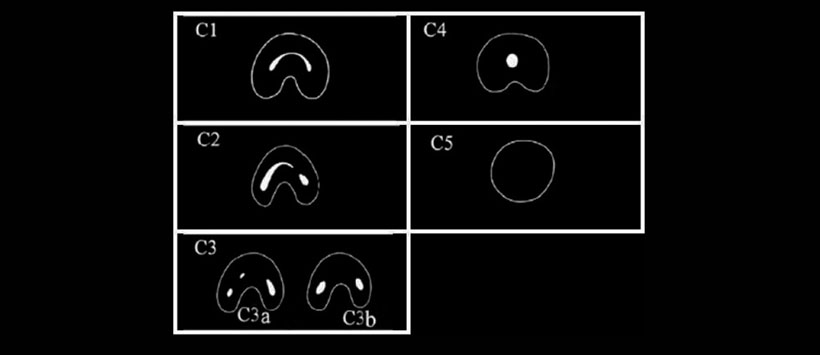

La primera molar mandibular de una sola raíz con un orificio continuo para 2, 3 o 4 conductos radiculares fue reportado por primera vez en un artículo dental por Cooke y Cox en 1979. Menton et al. sugirió por primera vez la clasificación de los conductos radiculares en forma de C en función de la forma de la sección transversal; sin embargo, no hubo una explicación clara para diferenciar los grupos 2 y 3. Fan et al. analizaron la morfología de los conductos radiculares en forma de C en los segundos molares mandibulares con el uso de micro TC y la técnica de Melton modificada, de la siguiente manera (Figura 1): C1: un canal radicular continuo en forma de C sin separación ni separación dividida, C2: un canal de raíz en forma de coma, lo que resulta en un conducto radicular no continuo en forma de C, C3: dos o tres conductos radiculares separados, C4: un solo conducto radicular con una sección transversal redonda u ovalada y C5: ausencia de cualquier cavidad del canal, siendo visible solo cerca del ápice